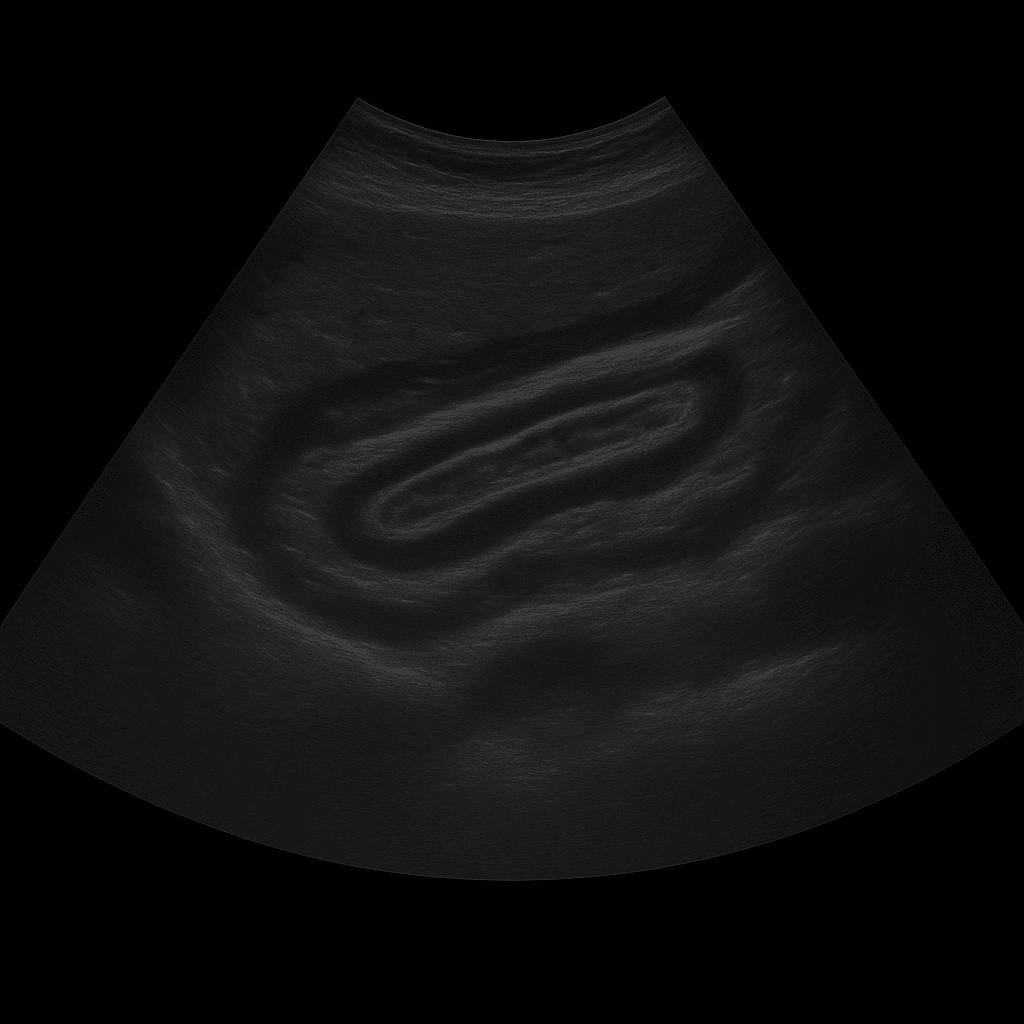

Ett ultraljud av buken används för att undersöka bukens inre organ såsom lever, gallblåsa, gallvägar, bukspottkörtel, mjälte, njurar och urinblåsa. Undersökningen utförs av specialistläkare inom radiologi och ger detaljerade bilder i realtid. Ultraljud buk används för att utreda smärta, svullnad, förändrade blodprover eller misstanke om sjukdom i bukorganen.

Undersökningen utförs när du ligger på rygg. En gel appliceras på huden och läkaren för ultraljudsproben över bukområdet för att bedöma de inre organen. Undersökningen tar cirka 20–30 minuter och är helt smärtfri. För bästa bildkvalitet bör du vara fastande i 4–6 timmar innan, eftersom luft och föda i tarmen kan påverka bildresultatet. Vid behov undersöks även urinblåsan fylld för att bedöma njurarnas avflöde.